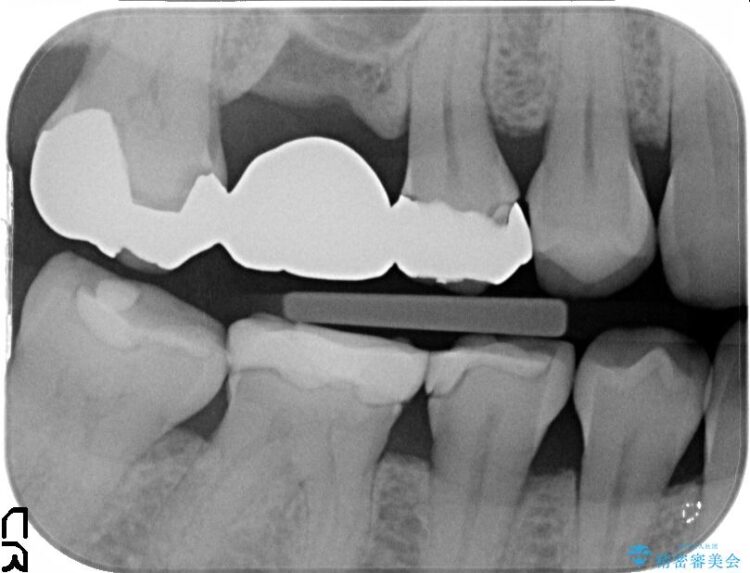

初診の際に撮影したレントゲンにて以前他院で治療していた詰め物が適合不良であることが判明し、再度治療をしてほしいとのご希望でした。

ぱっと見ただけでは特に問題ないように見えますが、レントゲンをよく確認すると詰め物と歯の間に隙間がはっきりと確認ができます。

適合不良であるインレーを放置するリスクを患者様へ説明してご納得いただいた上で、オールセラミックインレーで治療を行うこととしました。